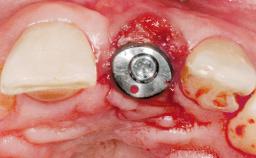

Late Placement of an Implant in a Maxillary Left Central Incisor Site

A 36-year-old female patient was referred for the replacement of the upper left central incisor (tooth 21), which had fractured. Although the tooth had been asymptomatic for many years, the crown began to loosen, at which time she presented to her dentist for an assessment. Teeth 21 and 22 had both been endodontically treated many years previously. She was a healthy individual and a non-smoker.

On examination, the patient had a low lip line and only displayed the coronal half of the anterior teeth when smiling.

The crown of tooth 21 was splinted to the adjacent teeth with composite resin, and the gingiva was inflamed.